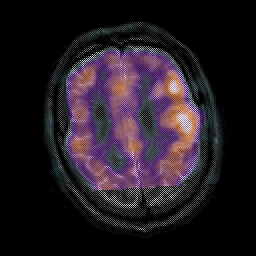

Subacute Stroke, overlay -- Slice #19

[Home][Help][Clinical] Slice 19

Click on sagittal image to select slice. Click on thin tickmark to change timepoint, or thick tickmark for overlay.